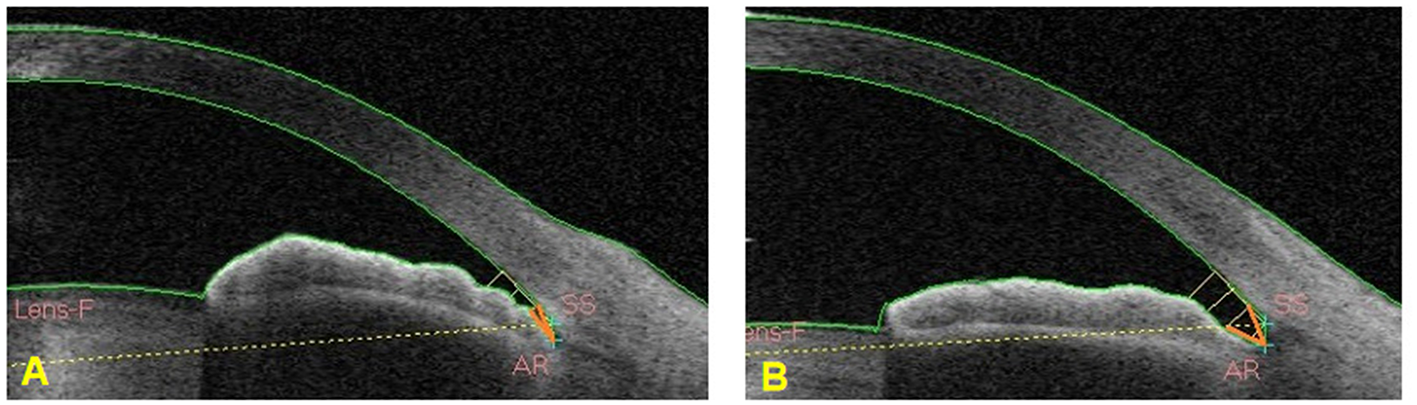

At the early stage of this study, a test classifier was developed that included a small sample and several ACA images. To test the accuracy of the classifier in distinguishing different widths of an open angle, we selected two different and independent test sets. Open angle images in the test set 1 were images with wider trabecular iris angle 250 um (TIA250) while open angle images in test set 2 were images with narrower TIA250. Images with TIA250 >25 degrees were selected in the test set 1 while images in the test set 2 were those with TIA250 ranging from 11 to 15 degrees (Figure 4).

Figure 4

TIA250 was marked by an orange angle. (A) The ACA image showed TIA250 between 11 and 15 degrees. (B) The ACA image showed TIA250 >25 degrees.